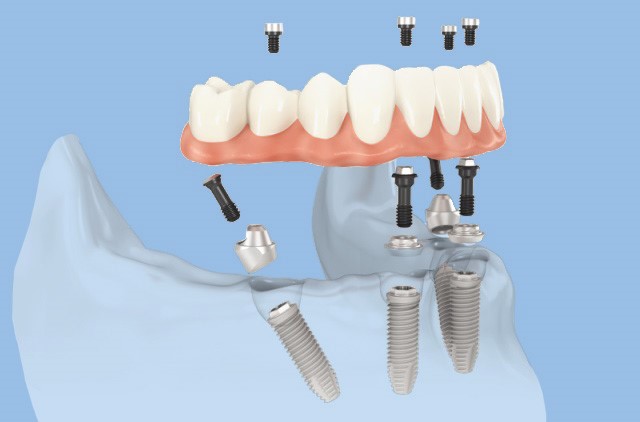

All-on-4 = Teljes foghiány pótlása csontpótlás nélkül, 4 implantátumon rögzített körhíddal

A kezelés célja: 4 db implantátumon rögzített csavarozható hídprotézis készítése.

A technika lényege, hogy, a fogmű viselésére alkalmas megfelelő méretű fogászati implantátumokat olyan szögben helyezzük el, hogy a meglévő csontformát és mennyiséget kihasználva a lehető legvastagabb csontban legyenek. Ez lehetővé teszi, hogy kevesebb fogászati implantátum csontpótlás nélkül is hosszú távon alkalmas legyen, a rágásból eredő nagy erőhatás elviselésére is.

A képek csak illusztrációk (a szájról készült fényképen cocr vázra égetett porcelán pótlás látható) a munkafolyamatok és a fogpótlás szerkezetének könnyebb megértése érdekében. Az ön fogpótlása csak hasonlóan fog kinézni, csak a jellege ugyanilyen. A szürke csavarozható elemek a mélyben látszódhatnak, a rózsaszín íny és a fogak átmenete hasonló lesz, de az elveszett csont és lágyrészek mennyisége, az íny lefutása, az implantátumok helyzete, helye mindenkinél más így a pótlás kinézete is változik.